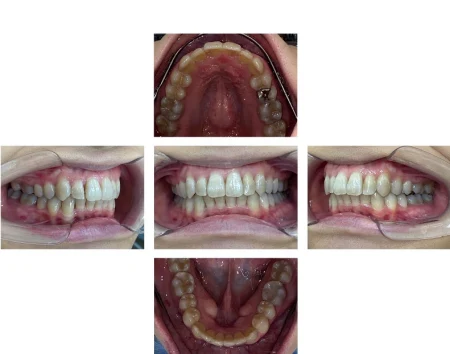

上下とも歯がまっすぐに並び、美しい口元になりました。

患者様にも「自信をもって笑えるようになった」と大変お喜びいただけました。

現在は、歯並びの後戻りを防止するための「保定装置」をご使用いただきながら経過を観察しています。